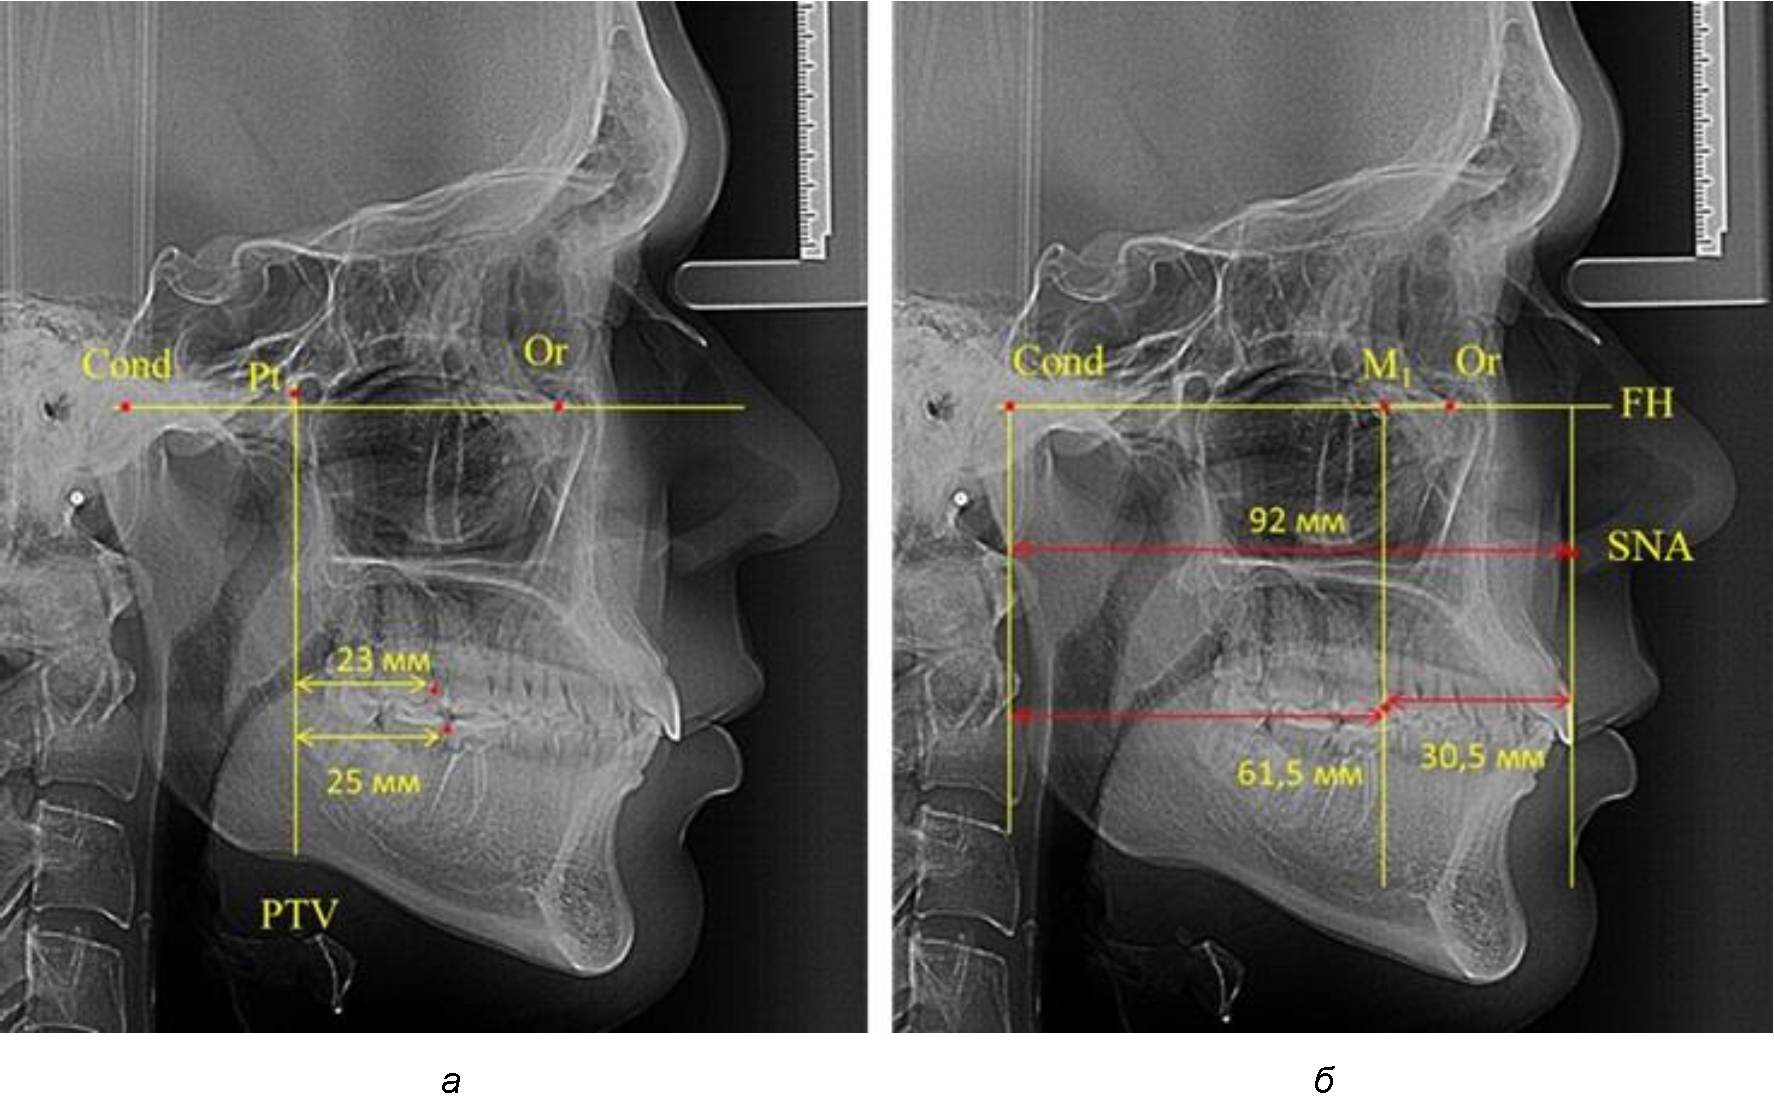

В то же время при увеличенном расстоянии от крыловидной вертикальной плоскости PTV до дистальной поверхности верхнего первого постоянного моляра, равное 23 мм, сагиттальный размер гнатического отдела составил 92 мм. При этом отношение кондилярно-спинального расстояния к кондилярно-молярному размеру (30,5), так же, как и при малых размерах, было близким к коэффициенту 1,5, что представлено на рис. 3.

Рис. 3. Особенности положения первых моляров по R. E. McDonald (а) и по предложенному методу (б) при увеличенном молярно-крыловидном расстоянии

Рентгенограмма 16-летнего ребенка, с реперными линиями и анализируемыми линейными параметрами по двум используемым методам, представлена на рис. 6.

Рис. 6. Особенности положения первых моляров по R. E. McDonald (а) и по предложенному методу (б) у ребенка 16 лет